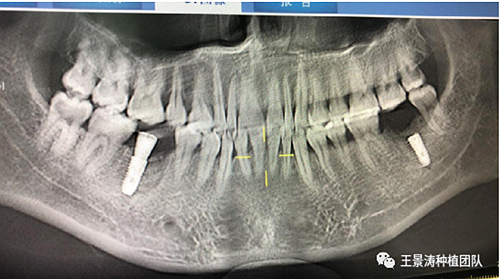

患者左側(cè)16慢性根尖周炎,17缺失。16根尖炎癥距上頜竇底較近,需內(nèi)提升,但是因為內(nèi)提升后骨質(zhì)較薄所致植入深度過深,埋入式植入。17非埋入式種植。后期效果均可。

術(shù)后一周

二期手術(shù)